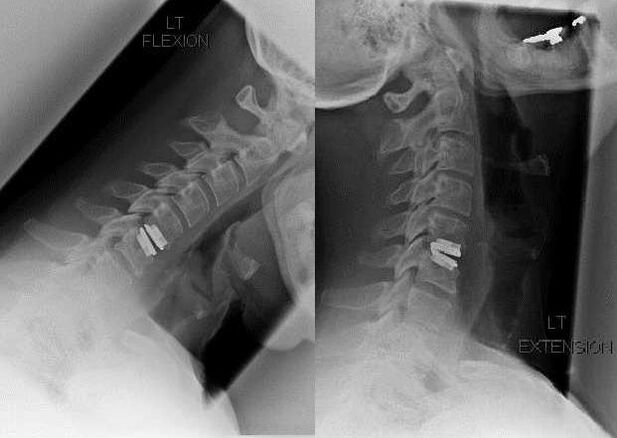

Sebészeti beavatkozás

A sebészeti beavatkozás indikációi közé tartozik a konzervatív kezelés hatástalansága, valamint a nyaki osteochondrosis szövődményei, például diszkogén myelopathia, vertebralis artéria szindróma és radicularis szindróma. A gerincvelő, az erek és a gerinc gyökereinek dekompressziója érdekében a következő műveleteket hajtják végre:

- laminectomia;

- laminotómia;

- foraminotómia;

- facetectomia;

- discectomia.

A műtét során a csontdarabok és szalagok kimetszhetők, a csigolyaközi porckorongok teljesen vagy részben eltávolíthatók. Kisméretű sérvnyúlványok esetén gyakran elvégzik a porckorong magjának lézeres párologtatását.

A csigolyaszerkezetek kimetszése után gyakran van szükség a gerincmozgási szegmensek stabilizálására gerincfúzióval vagy csont- és dermális autograftok telepítésével.